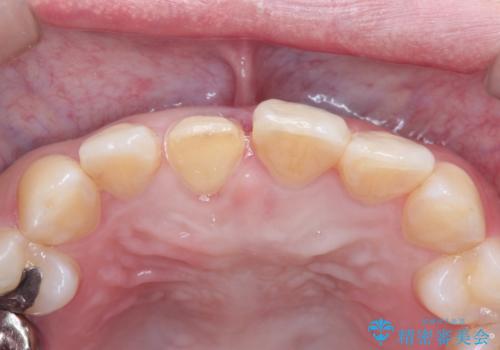

- 前歯の歯並びが気になるとのことで来院されました。

右上の1番目の歯が内側に入り込んでしまっており、その歯がの先端がすり減ってしまっていました。

インビザラインによる矯正治療で前歯の歯並びを改善し、セラミッククラウン装着により歯の形態の回復をする計画としました。